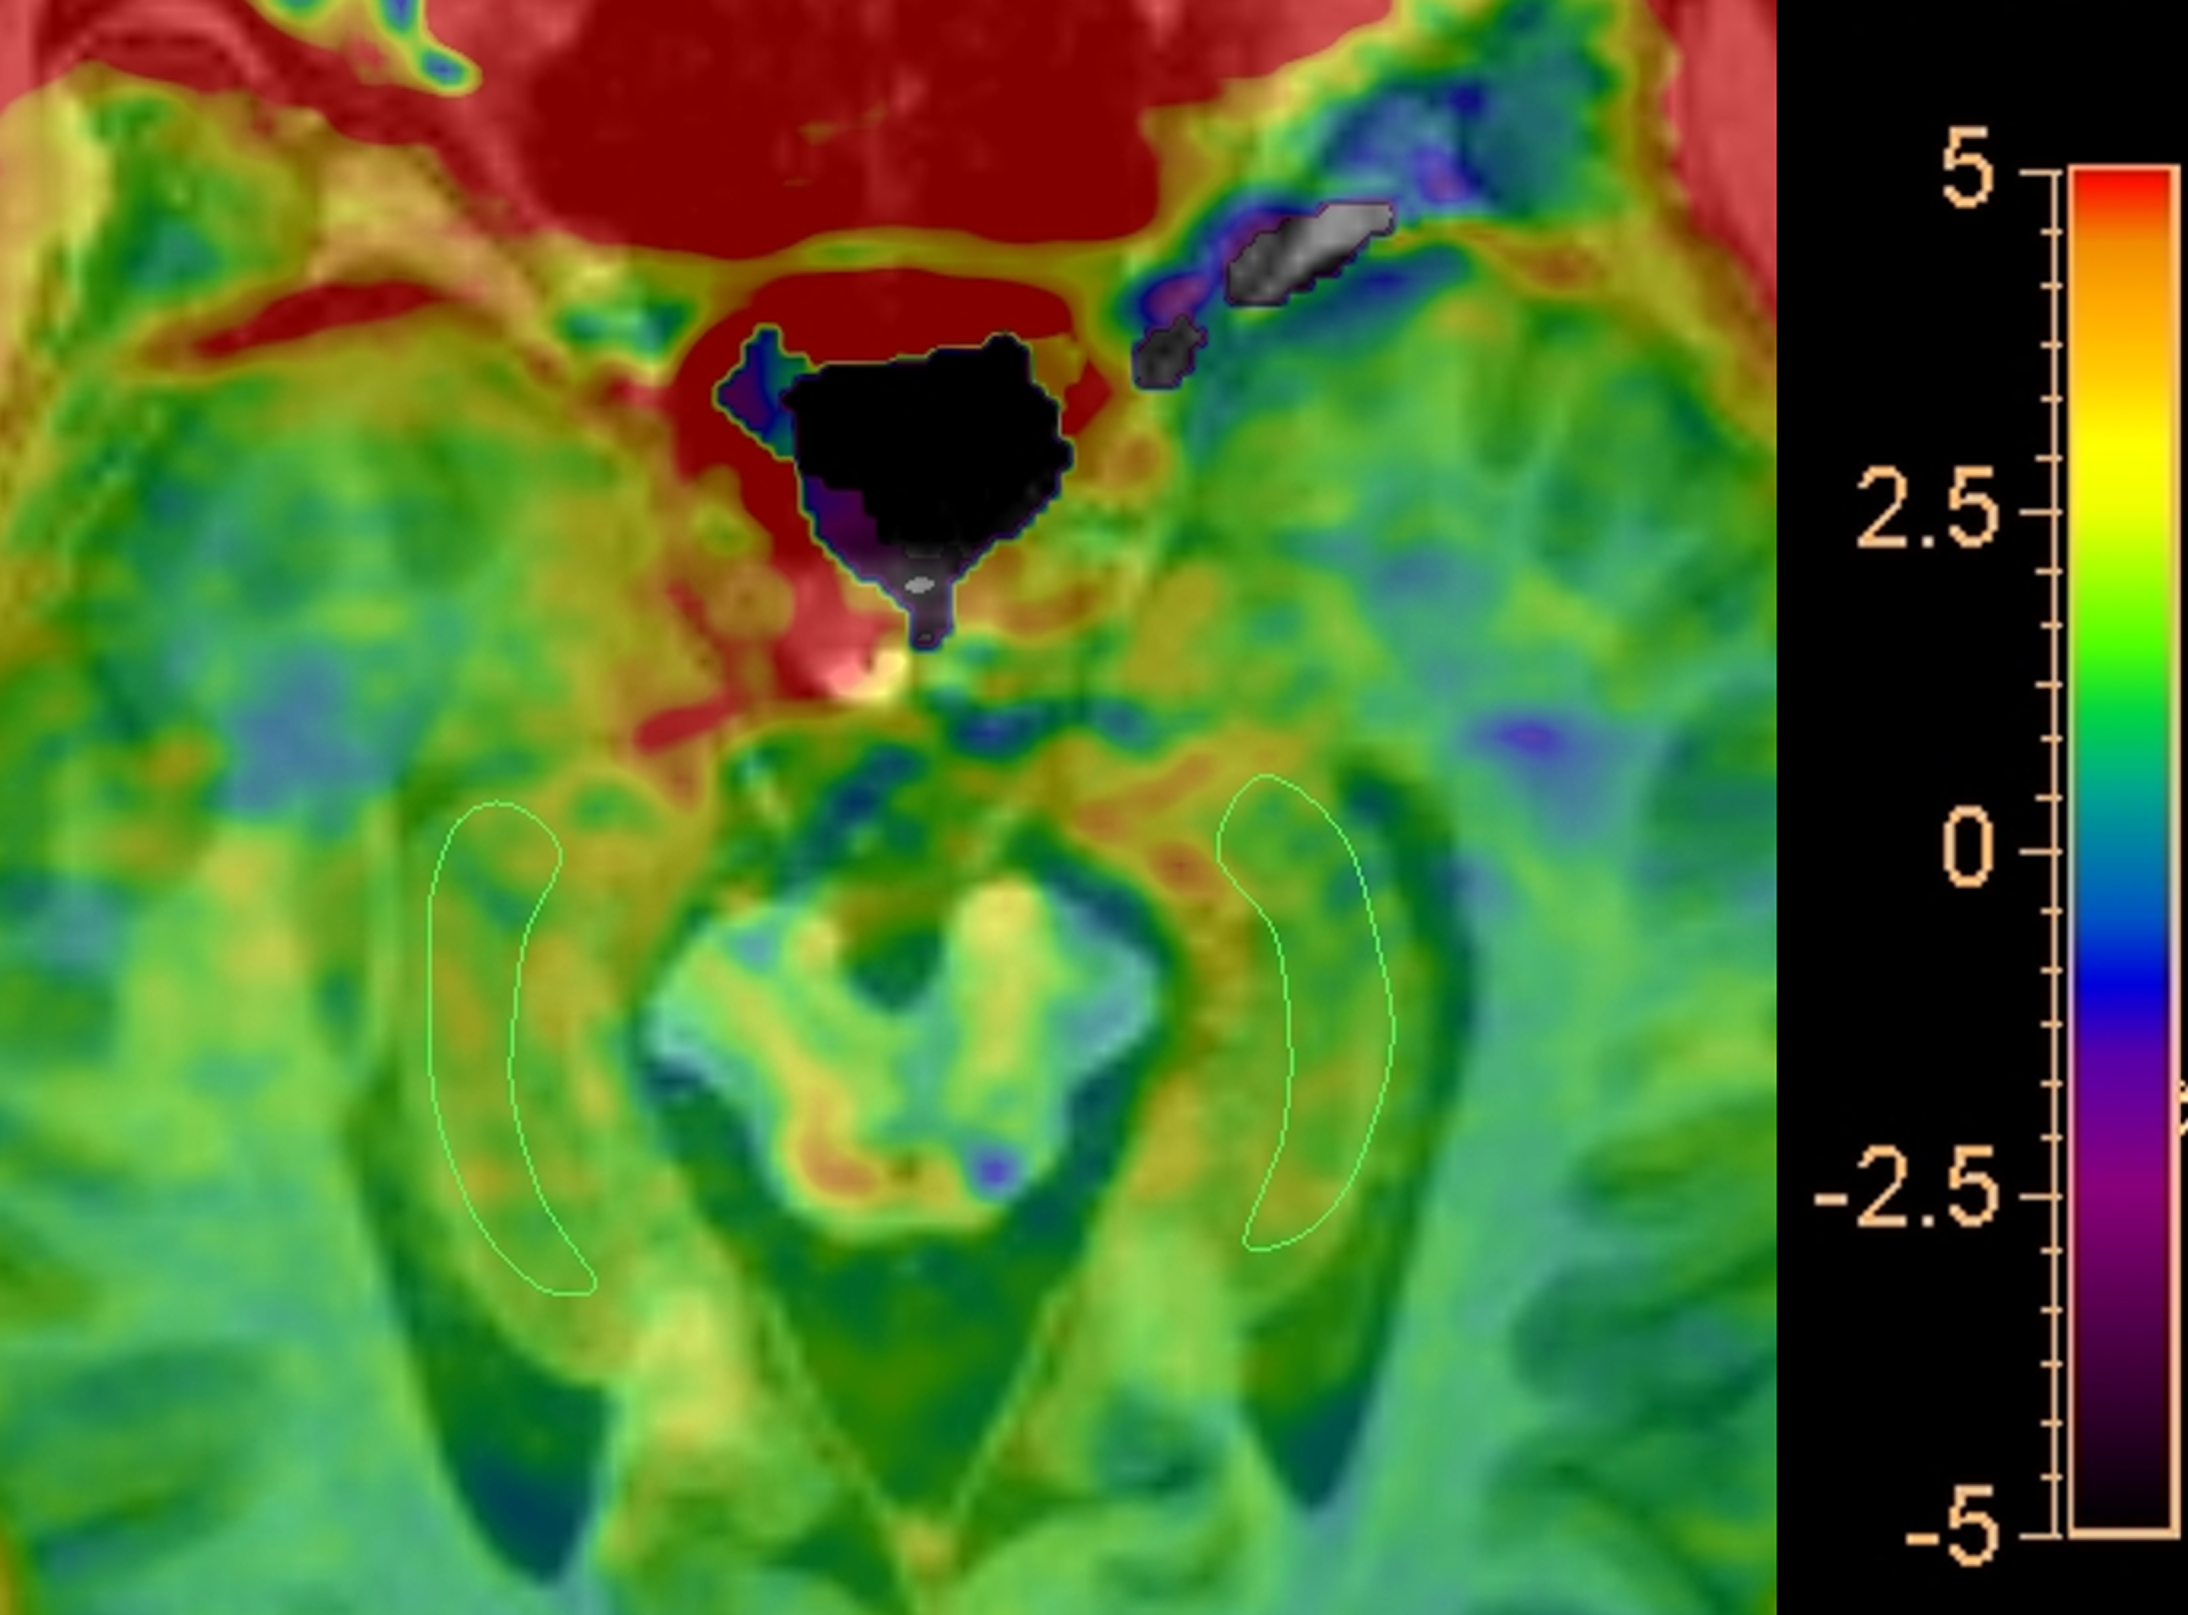

Comparison of APTw values between HC group and aMCI group Compared with HCs, aMCI patients showed higher APTw values in the right hippocampus (P=0.006).

Representative regions of interest (ROIs) for APT analysis Delineate ROIs of the bilateral hippocampus in the maximum cross-sectional layer of T1 weighted image with APTw overlay.